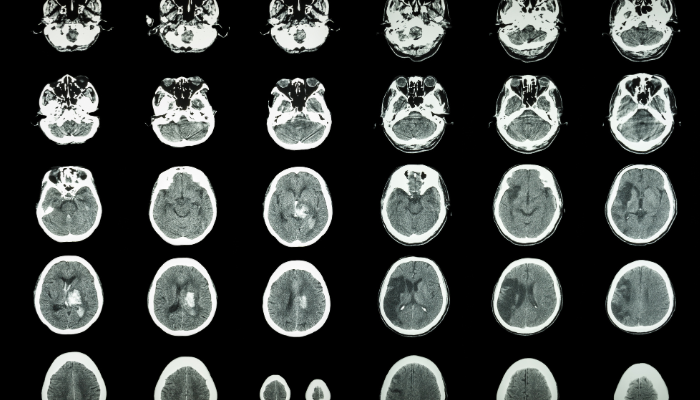

A cerebral vascular attack (CVA), is when something has stopped oxygenation to brain tissue. This can be caused by bleeding into the brain (hemorrhagic stroke) or when blood supply is disrupted/stopped in the brain causing an ischemic stroke.

Knowing why or what caused the CVA is an important factor for post stroke care. The two most common types of stroke are large vessel and small vessel stroke.

Large vessel or cardioembolic stroke is most commonly caused from an irregular heart rhythm, atrial fibrillation ("Afib") being the most common. Large vessel strokes can also be caused by plaque in the arteries, intracranial atherosclerosis or from a carotid artery stenosis.

Small vessel strokes are most commonly in the brainstem and are caused by risk factors of hypertension, diabetes, hyperlipidemia, and smoking. These are typically smaller strokes but can often have the most debilitating symptoms.